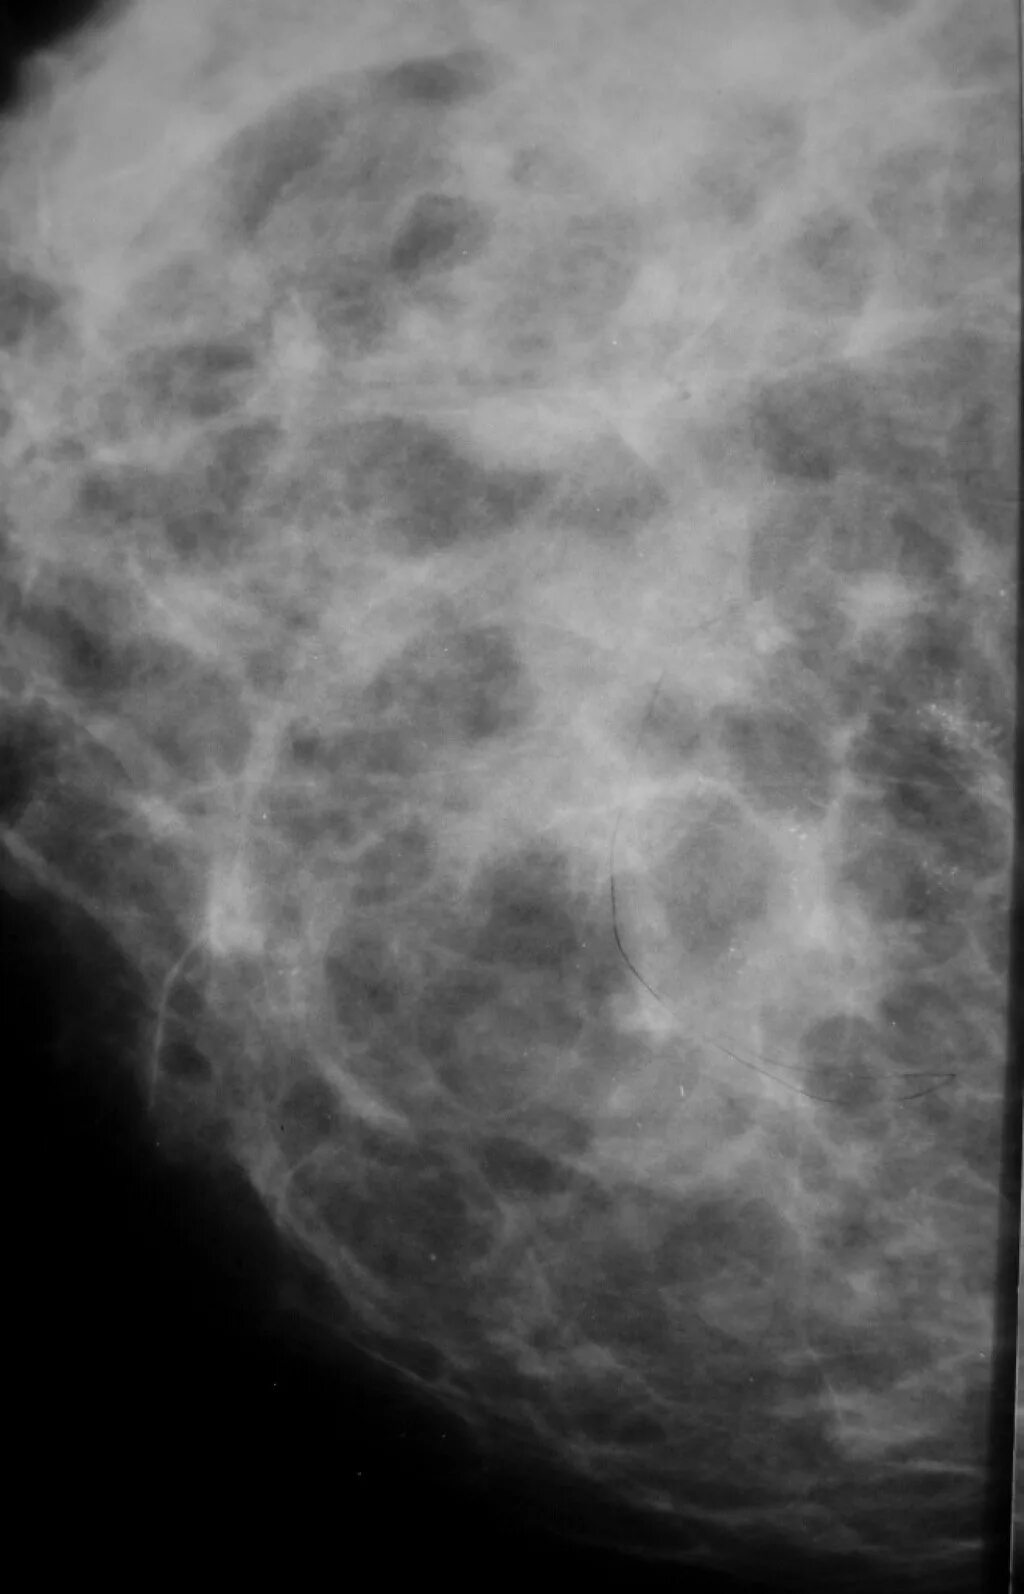

Выраженный диффузный фиброаденоматоз молочных